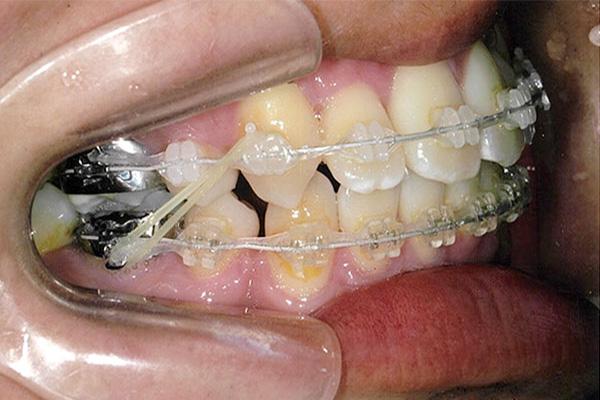

1年5ヶ月後